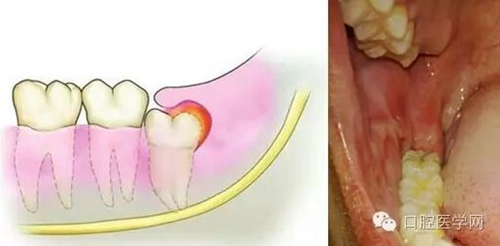

(1)冠周炎:智齒因阻生而使牙冠不能完全外露,牙冠周圍的牙齦成袋狀,極易積存食物、滋養(yǎng)細(xì)菌。當(dāng)全身抵抗力下降時引起急性冠周炎。

(2)間隙感染:冠周炎的炎癥可能進一步向肌肉間隙內(nèi)擴散造成間隙感染。

(3)第二磨牙齲壞:向前傾斜的阻生智齒,因經(jīng)常在鄰牙間積存食物,易發(fā)生鄰牙(下頜第二磨牙)齲壞。